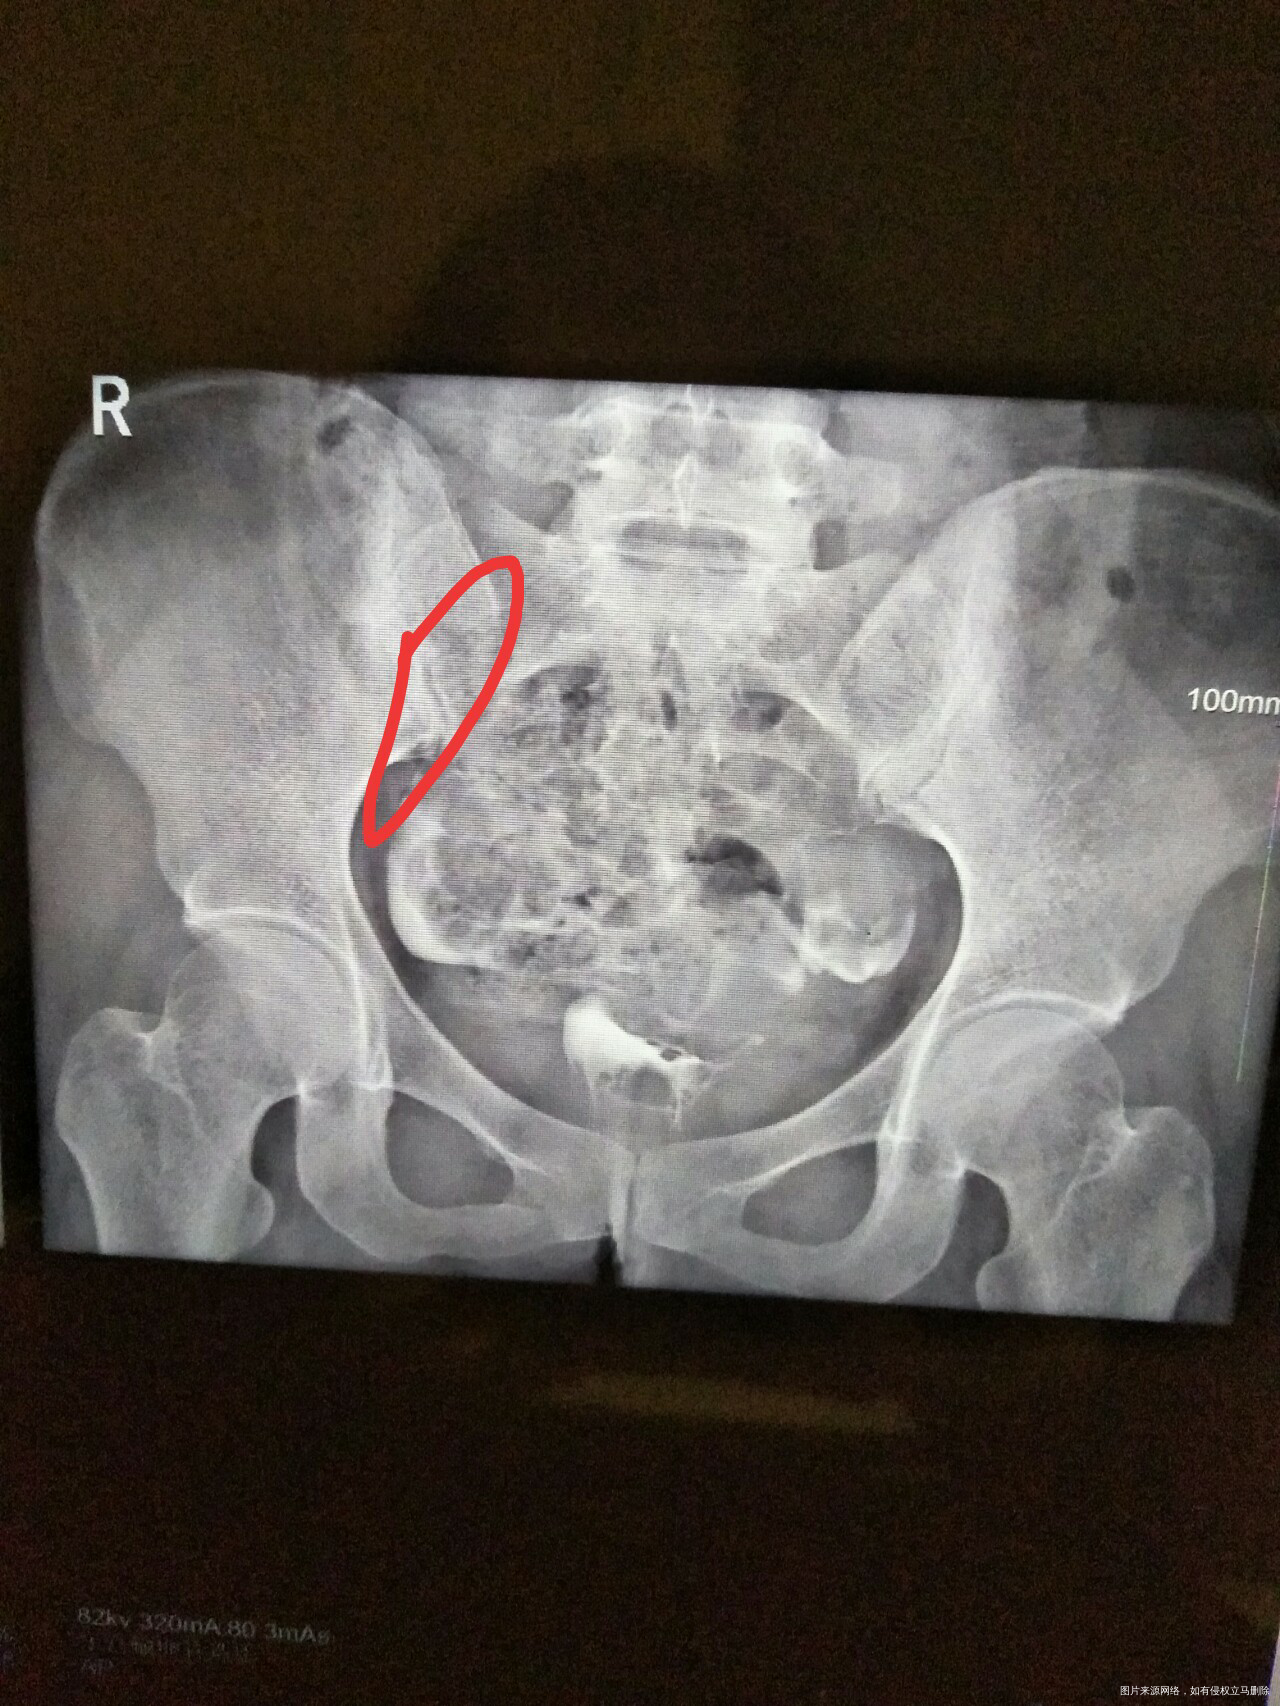

帮我分析下,红色圈这边是什么情况,另一什么情况?片子是不是方向是反的?红色这边是身体哪边的输卵管?谢谢,麻烦医生了

你好,那是右边。图片有写R。造影会有报告单,就会写明造影结果。祝你好孕。如果我的建议对您有帮助,请记得选择采纳

你好!根据图片显示右侧不通畅

你好!根据图片显示右侧输卵管近端不通畅。

你好,根据图片显示右侧输卵管近端不通畅。